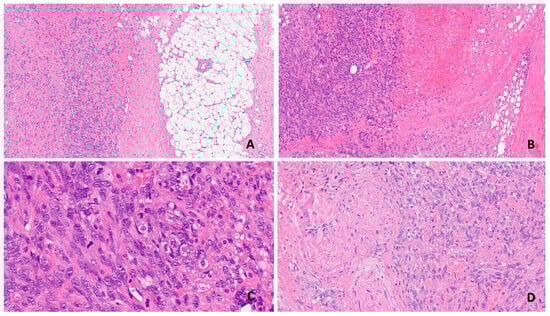

2. Angiosarcoma: Histopathology of a Rare and Insidious Disease

2.1. Pathological Features

2.2. Differential Diagnosis